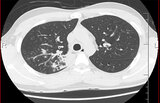

マイコプラズマに感染した患者の体内

マイコプラズマに感染した患者の体内(光学顕微鏡像)